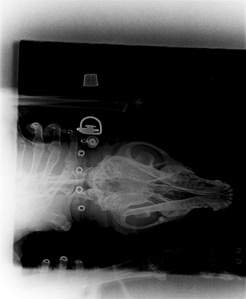

23 марта 2015 собаку нашла соседка с поврежденным глазом. Было принято решение везти его в клинику ВЕЛЕС и показать офтальмологу. Первичный осмотр показал сильное повреждение глаза в следствии травмы. Был сделан снимок, где было видно инородное тело, предположительно пуля от пневматического оружия. 26 марта 2015 Малыш в срочном порядке был прооперирован, операция длилась три часа. Большое Спасибо Сидоровой Оксане Николаевне и Жуйкову Андрею Михайловичу, они оперировали Малыша, и всему персоналу клиники. Пулю к сожалению пока достать не удалось, было принято решение "отремонтировать" глаз (попытаться сохранить зрение), а затем сделать вторую операцию по извлечению пули. На данный момент Малыш находится на передержке у неравнодушной женщины.